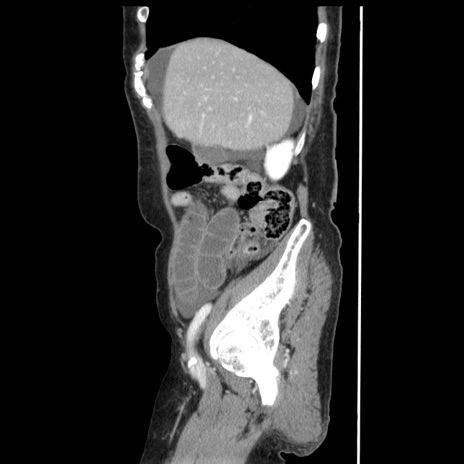

症例1(矢状断像)

【症例】80歳代女性

【主訴】腹痛

【現病歴】8時間前から腹痛あり来院。

【既往歴】糖尿病、脂質異常症、子宮体癌にて子宮全摘術

【身体所見】意識清明・会話良好だが腹痛で苦悶様、全腹部にわたって反跳痛と圧痛あり

【データ】WBC 13600、CRP 0.14、LDH 224、CK 90